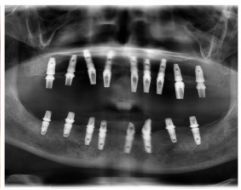

种牙后X光片,未戴冠。

通过X光片可以看到,医生虽然尽量设计连冠种植,但还是用了十七个植体,尽管已经是多次调整后的最精简方案,但手术时长依然长达一天。位老先生之前在另一家医院咨询时,医生给的方案是种二十二个植体,光是种植费用就令人大呼“害怕”了。